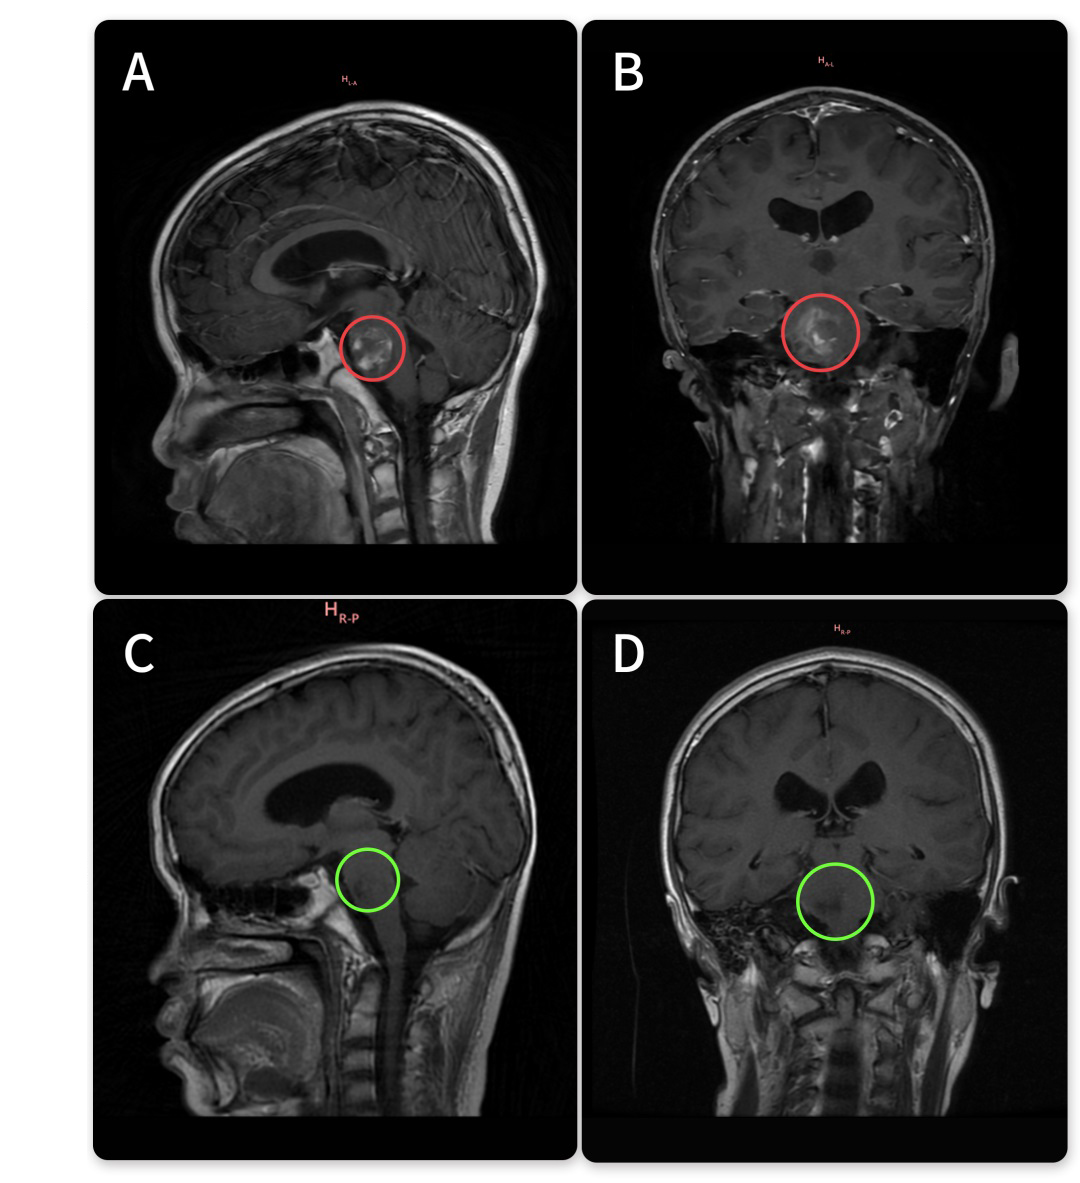

68岁女性•右侧基底节海绵状血管瘤

术前症状:多次出血,对于脑干海绵状血管瘤患者来说,是较不愿意看到的情况。而对于一个60多岁的基底节海绵状血管瘤患者来说,对手术这个的根治方式犹豫不决。68岁的柯女士,突然舌头麻木,晨起后出现眩晕,医院检查后结论为椎体骨质增生及脑供血不足。2022年再次进行手术去医院行核磁检查后发现海绵状血管瘤,医生建议定期复查MRI。然而含血病灶逐年增大,从22年的18*19mm到2023年的24*19mm,但是多名专家表示不赞成手术治疗,更是明确表示术后偏瘫失语可能性大。远程咨询INC巴特朗菲教授之后,教授给出了的评估。柯女士和家人商量后原本想要等巴教授下一次来华时再进行手术,然而谁也没想到9月底教授在华手术期间柯女士症状开始出现波动,发作频繁,当巴教授查看核磁图像后,发现病灶较前增大,结合患者病情有进展,告知患者随时会有出血风险,需要立即手术。柯女士和家人与巴教授紧急视频沟通之后,决定提前手术,果断买飞机票来到苏州。

治疗过程:10月1日,在苏州大学附属独墅湖医院,巴教授顺利完成手术,无任何新发神经功能损伤。

术后情况:术后2天巴教授查房时,柯女士精神状态好,已经可以下地走路。看到前来查房的巴教授,柯女士激动,亲切拥抱感谢巴教授,终于摆脱了危险的基底节海绵状血管瘤的她满怀感激得握住巴教授的手说道,“我要看看巴教授这双神奇的大手,这是上帝之手,巴教授感谢你!”